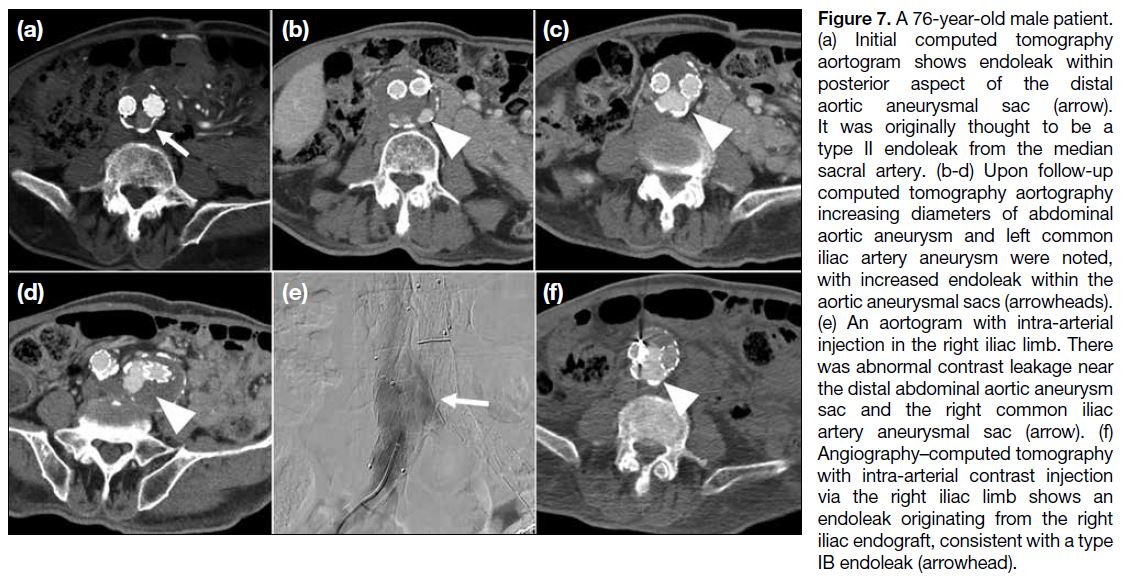

A 76-year-old male patient with infrarenal abdominal

aortic aneurysm and left common and internal iliac artery

aneurysms was managed with endovascular aneurysm

repair. A diagnostic aortogram was performed 1 year

after endovascular aneurysm repair to clarify the type

and site of endoleak. 5Fr Multipurpose catheter (Merit

Medical, South Jordan [UT], United States) was then navigated to the left iliac limb and superior mesenteric

artery, with angio-CT angiogram performed to exclude

other endoleak sites. The patient was managed with

extension of the right iliac limb endograft (Figure 7).

Figure 7. A 76-year-old male patient.

(a) Initial computed tomography

aortogram shows endoleak within

posterior aspect of the distal

aortic aneurysmal sac (arrow).

It was originally thought to be a

type II endoleak from the median

sacral artery. (b-d) Upon follow-up

computed tomography aortography

increasing diameters of abdominal

aortic aneurysm and left common

iliac artery aneurysm were noted,

with increased endoleak within the

aortic aneurysmal sacs (arrowheads).

(e) An aortogram with intra-arterial

injection in the right iliac limb. There

was abnormal contrast leakage near

the distal abdominal aortic aneurysm

sac and the right common iliac

artery aneurysmal sac (arrow). (f)

Angiography–computed tomography

with intra-arterial contrast injection

via the right iliac limb shows an

endoleak originating from the right

iliac endograft, consistent with a type

IB endoleak (arrowhead).